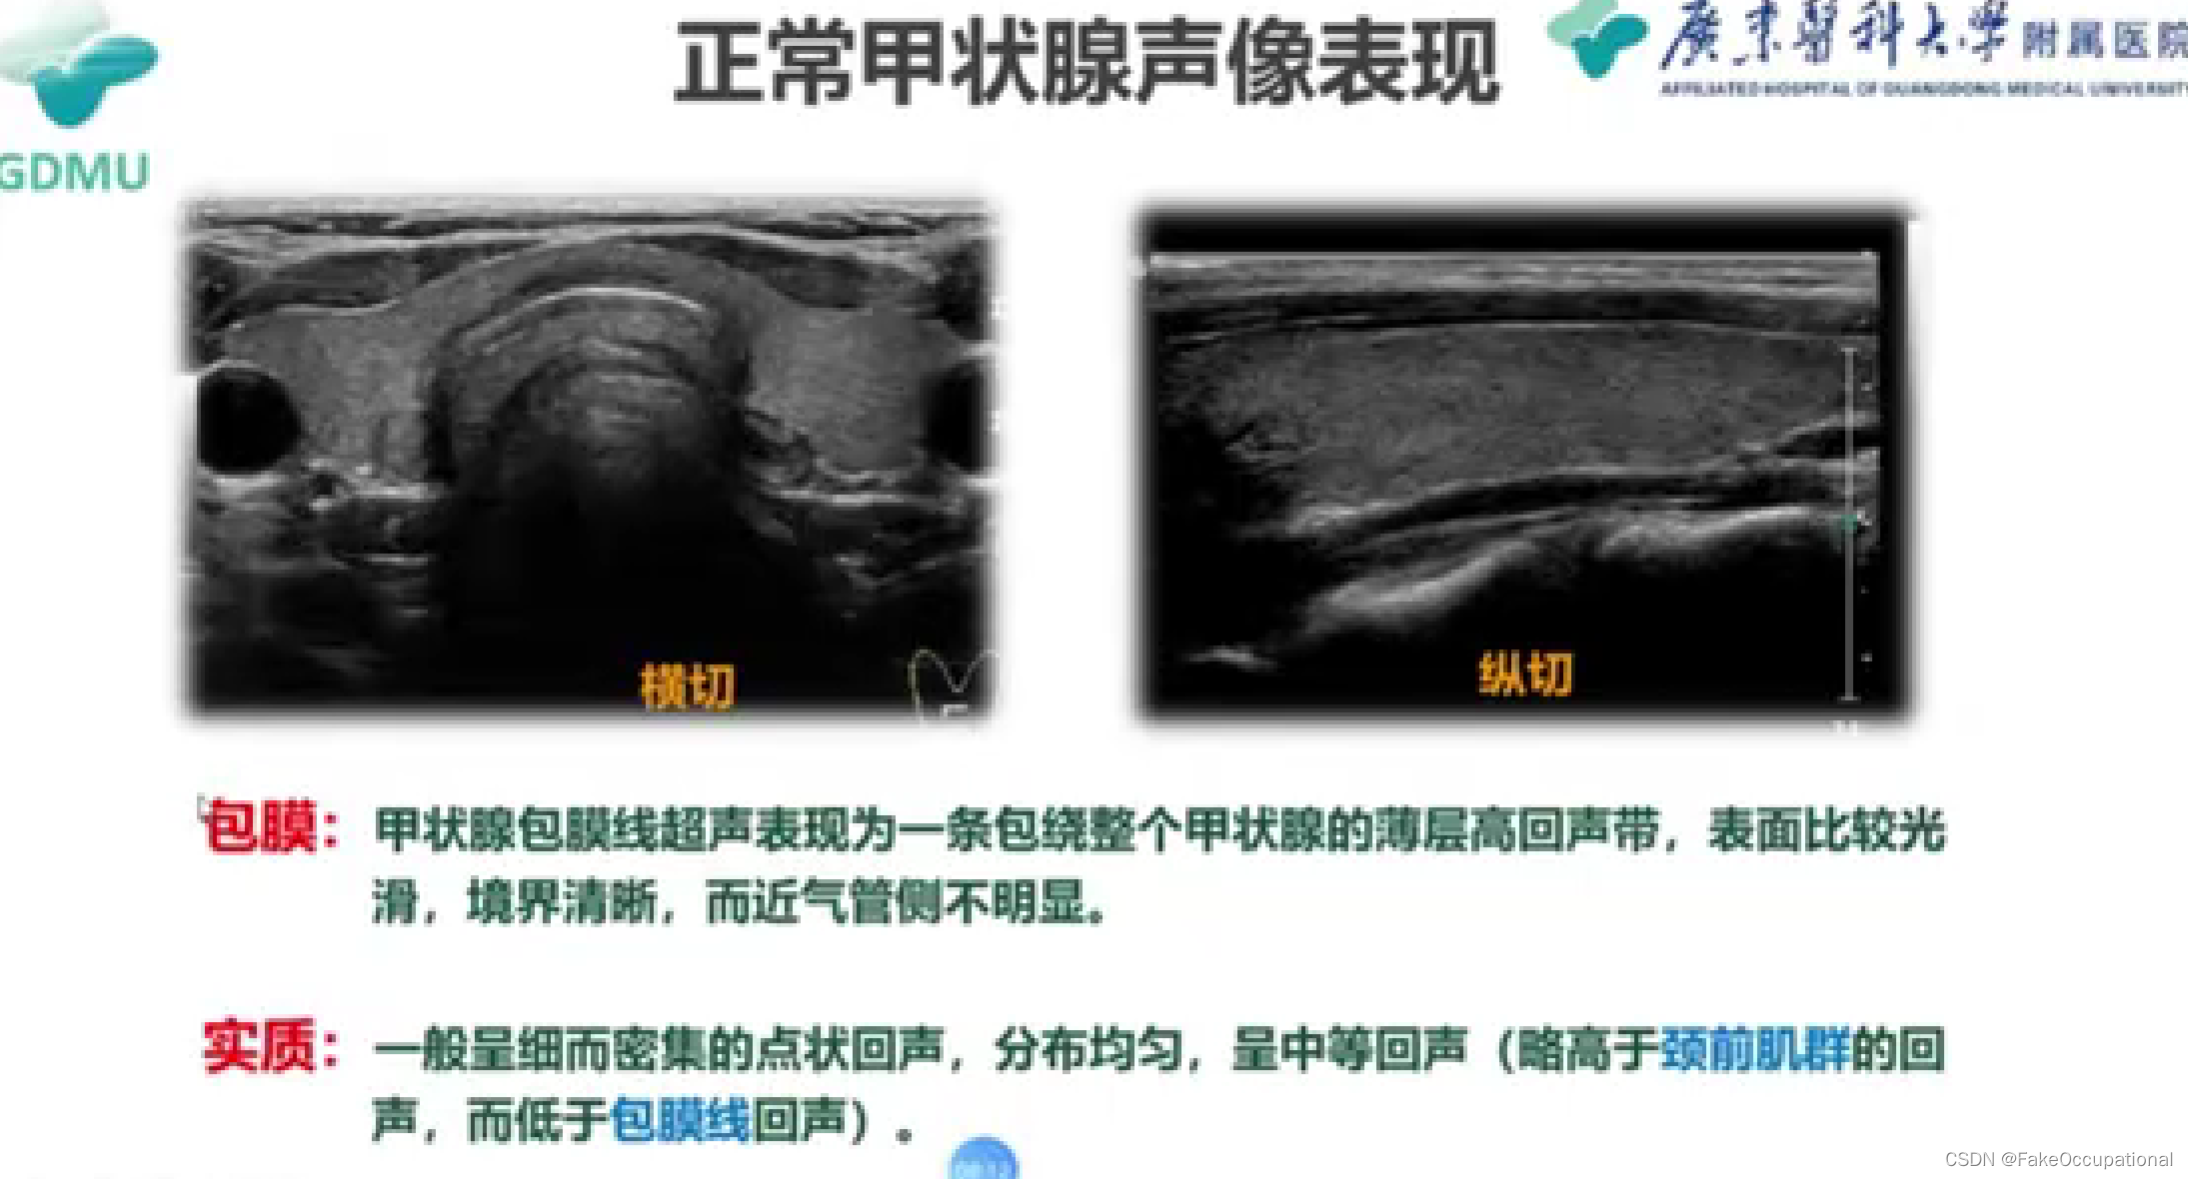

甲状腺超声